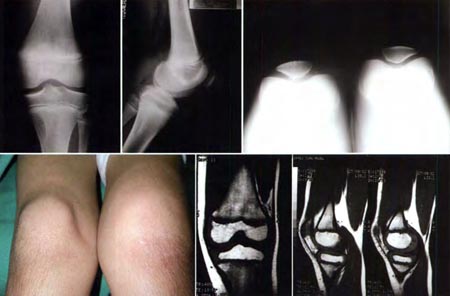

Paciente de sexo masculino de 10 años de edad que consulta por dolor, tumefacción e impotencia funcional de rodilla derecha. Al examen físico presenta hipotrofia de cuádriceps, choque rotuliano (+) y maniobras de estabilidad negativas. Por lo que se decide realizar una artrocentesis, extrayéndose 35cm3 de líquido hemático (cultivo negativo). Es controlado por Reumatología quien descarta TBC y artritis reumatoidea. Se solicita RMN y se realiza biopsia artroscópica de la sinovial que confirma el diagnóstico de SVNP. El paciente es intervenido quirúrgicamente por artroscopía a los de 10 meses de la consulta inicial. Al último control (60 meses de seguimiento) se mantiene asintomático con una función articular completa (Rango de movilidad 0-130) y sin recurrencia clínica de la lesión. (Fig. 1)

Figura 1.: Paciente de sexo masculino de 10 años de edad que consulta por dolor, e impotencia funcional de rodilla izquierda. A) Radiografías sin hallazgos patológicos de relevancia, B) RMN, C) Aspecto clínico donde se objetiva marcada tumefacción y limitación del rango de movilidad. D) Imagen artroscópica característica de SVNP: Nódulos de color amarillo ocre localizados en el compartimento anterior, E) Estética de los 4 portales utilizados, F) Rango de movilidad completo a los 4 años de postoperatorio.